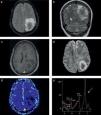

Absceso cerebral bacteriano inespecífico, confirmado luego del drenaje quirúrgico. Los cortes seleccionados de la RM en el plano axial demuestran la utilidad de (a) la secuencia de susceptibilidad magnética, (b) la SE ponderada en T1 con contraste, (c) la difusión y (d) el mapa de ADC. En la susceptibilidad magnética se identifica el aspecto típico de la cápsula bacteriana con un patrón en diana o de doble pared, debido al depósito ordenado de productos de degradación de la hemoglobina. La lesión presenta el típico realce en anillo fino, regular, completo y sin nódulos, con un centro necrótico con un intenso fenómeno de restricción en la difusión.

Se ha establecido la presencia de un intenso fenómeno de restricción en el centro de los AC bacterianos inespecíficos, que ha sido relacionada con la viscosidad del pus y su escasa celularidad18,19(fig. 2).

La presencia de restricción en una lesión con realce en anillo permite establecer el diagnóstico de AC bacteriano (con niveles de especificidad cercanos al 100%) y lo diferencia, sobre todo, de lesiones tumorales con necrosis o contenido quístico18,20,21 (fig. 4). Incluso, este hallazgo se ha señalado como patognomónico del AC, a pesar de que puede encontrarse en otro tipo de lesiones, como algunas metástasis con contenido de alta viscosidad o glioblastomas con hemorragia22.